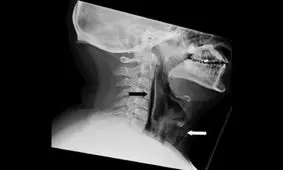

پزشکان تاکید میکنند هرگز جلوی عطسه خود را نگیرید. مردی انگلیسی به این توصیه عمل نکرد، گلویش سوراخ شد و مجبور شد یک…